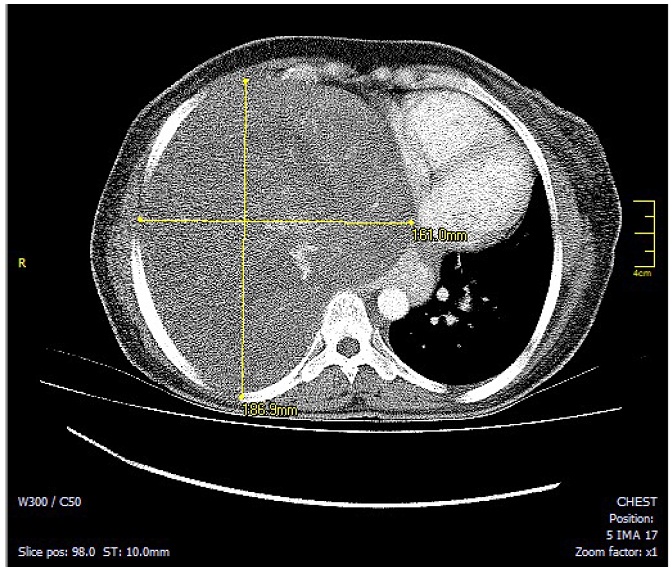

La radiografía de tórax inicial evidenció una opacidad que ocupaba el 70 % del hemitórax derecho, la tac contrastada de tórax evidenció una gran masa sólida de contornos lobulados que comprometía el 70 % del hemitórax derecho de origen extrapulmonar, heterogénea y con densidad de tejidos blandos, que desplazaba el mediastino y comprimía el corazón (figuras 1 y 2). Las dimensiones de la masa eran 16 x 18 x 22cm. Los diagnósticos planteados por el radiólogo fueron teratoma, tumor fibroso pleural o secuestro pulmonar. La histopatología de la muestra, obtenida por biopsia percutánea con aguja cortante de la lesión, reportó un tumor fusocelular de aspecto benigno que pudiera tratarse de un tumor fibroso de la pleura; posteriormente, la inmunohistoquímica confirmó el diagnóstico por inmunoreactividad de las células tumorales para bcl2, cd34, cd99 y stat6 compatible con un tumor fibroso solitario.

Nota: muestra el tfsp gigante que desplaza el mediastino y comprime la aurícula derecha.

Nota: evidencia el tfsp gigante que desplaza el mediastino y comprime la aurícula derecha.